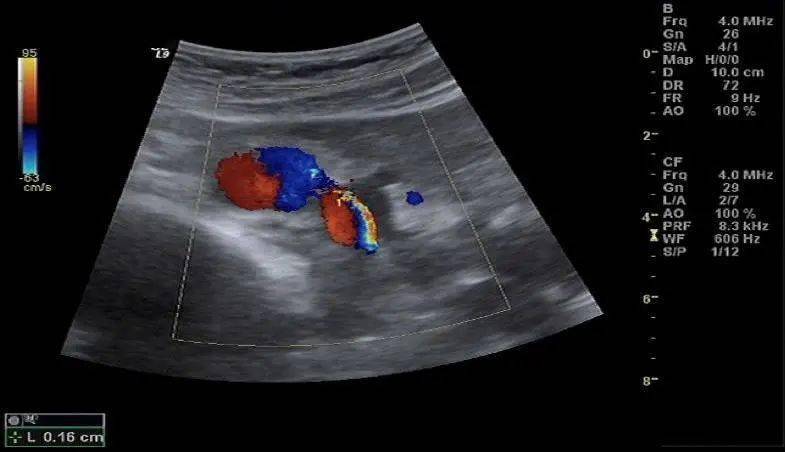

正常肾血流超声图像:箭头为肾门部,红蓝信号提示两条主干血管肾动脉及

新技术电诊科开展肾动脉彩色多普勒超声检查